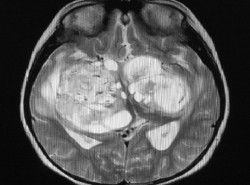

Identifican un grupo de células inmunitarias que esculpen las neuronas inhibidoras para regular el cableado del cerebro

Una investigación en ratones ha revelado cómo un subconjunto de células inmunes altamente especializadas modulan el cableado cerebral mediante sinapsis inhibidoras dirigidas con precisión. El trabajo profundiza la comprensión del repertorio versátil de microglia, las células inmunes del cerebro y los recolectores de basura residentes. Los resultados sientan las bases para el desarrollo de terapias para afecciones psiquiátricas y del neurodesarrollo marcadas por defectos en la función sináptica.